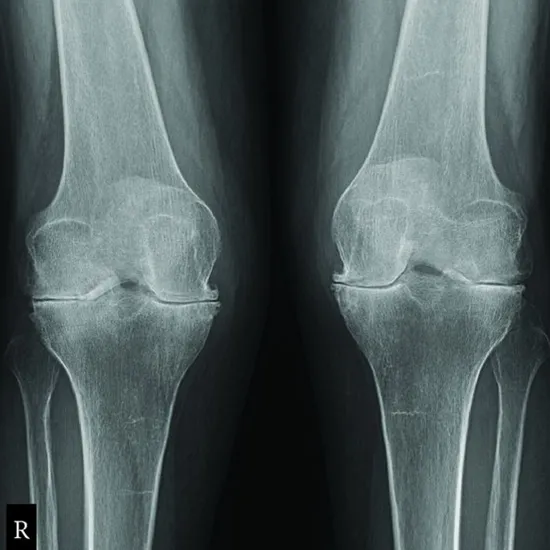

The oblique knee view is an extra projection that is asked for when more information about the knee joint is needed. There is both an internal and an external oblique in this view.

Right knee Internal and external oblique views of the knee can show problems like fractures and bone changes caused by wear and tear.